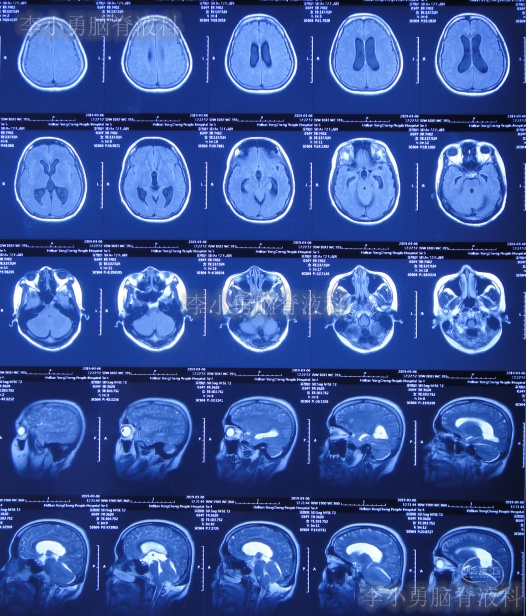

入院当天头颅CT示小脑扁桃体下疝减压术后,枕下可见低密度影。脑室系统稍扩张(图-12);颈椎核磁脊髓可见空洞形成(片子丢失)。

图-12:2019年3月19日入院时头颅CT

图-13:入院当天术后头颅CT

入院治疗3天即2019年3月22日,头痛减轻(图-14),查头颅CT示较入院时缩小(图-15)。

图-15:2019年3月22日头颅CT

入院治疗42天即2019年5月9日,头痛和体温均已完全正常近1月,查颈椎核磁示脊髓空洞有变小(图-16)。

图-16:2019年5月9日颈部核磁

入院治疗48天即2019年5月15日,进行了右侧脑室-腹腔分流术(图-17)。

图-17:2019年5月15日头颅CT